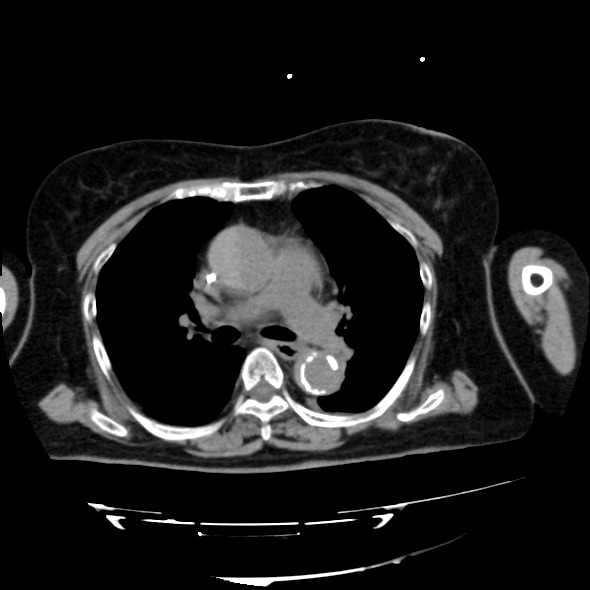

急性大動脈解離の造影CT

70歳代、女性、54kg、Stanford A型急性大動脈解離

症例は70歳台女性。胸背部痛を主訴に近医を受診し、単純CTを撮像したところ、Stanford A型急性大動脈解離を認めたため、加療目的に当院へ転院搬送となった。既往に慢性腎臓病があり、Cre 2.43mg/dL、eGFR 15.7と高度腎機能障害を認めたが、リスクベネフィットを検討した結果、術前精査のために造影CTが施行された。解離の範囲や造影剤のエントリー部位を同定することができた。

造影CTは急性大動脈解離の診断において最重要の検査であり、真腔と偽腔の描出、エントリー部位や偽腔内血栓の有無を評価できる。また、MPRや3D再構成を用いることで大動脈全体や末梢血管の状態を把握でき、手術やInterventional Radiologyによる手技前の血管解剖評価にも有用である。さらに、造影効果不良域の検出、ULP(ulcer-like projection)、臓器梗塞も早期に発見可能である。このように、造影CTは非侵襲的で短時間で行えるため、緊急疾患である急性大動脈解離に最適なモダリティといえる。一方で注意点は、造影剤アレルギーや腎障害など副作用への配慮、適切なプロトコル設計が求められる点である。造影CTは急性大動脈解離の確定診断と治療方針決定に不可欠であり、有効性を活かしつつリスク管理を徹底して施行する必要がある。